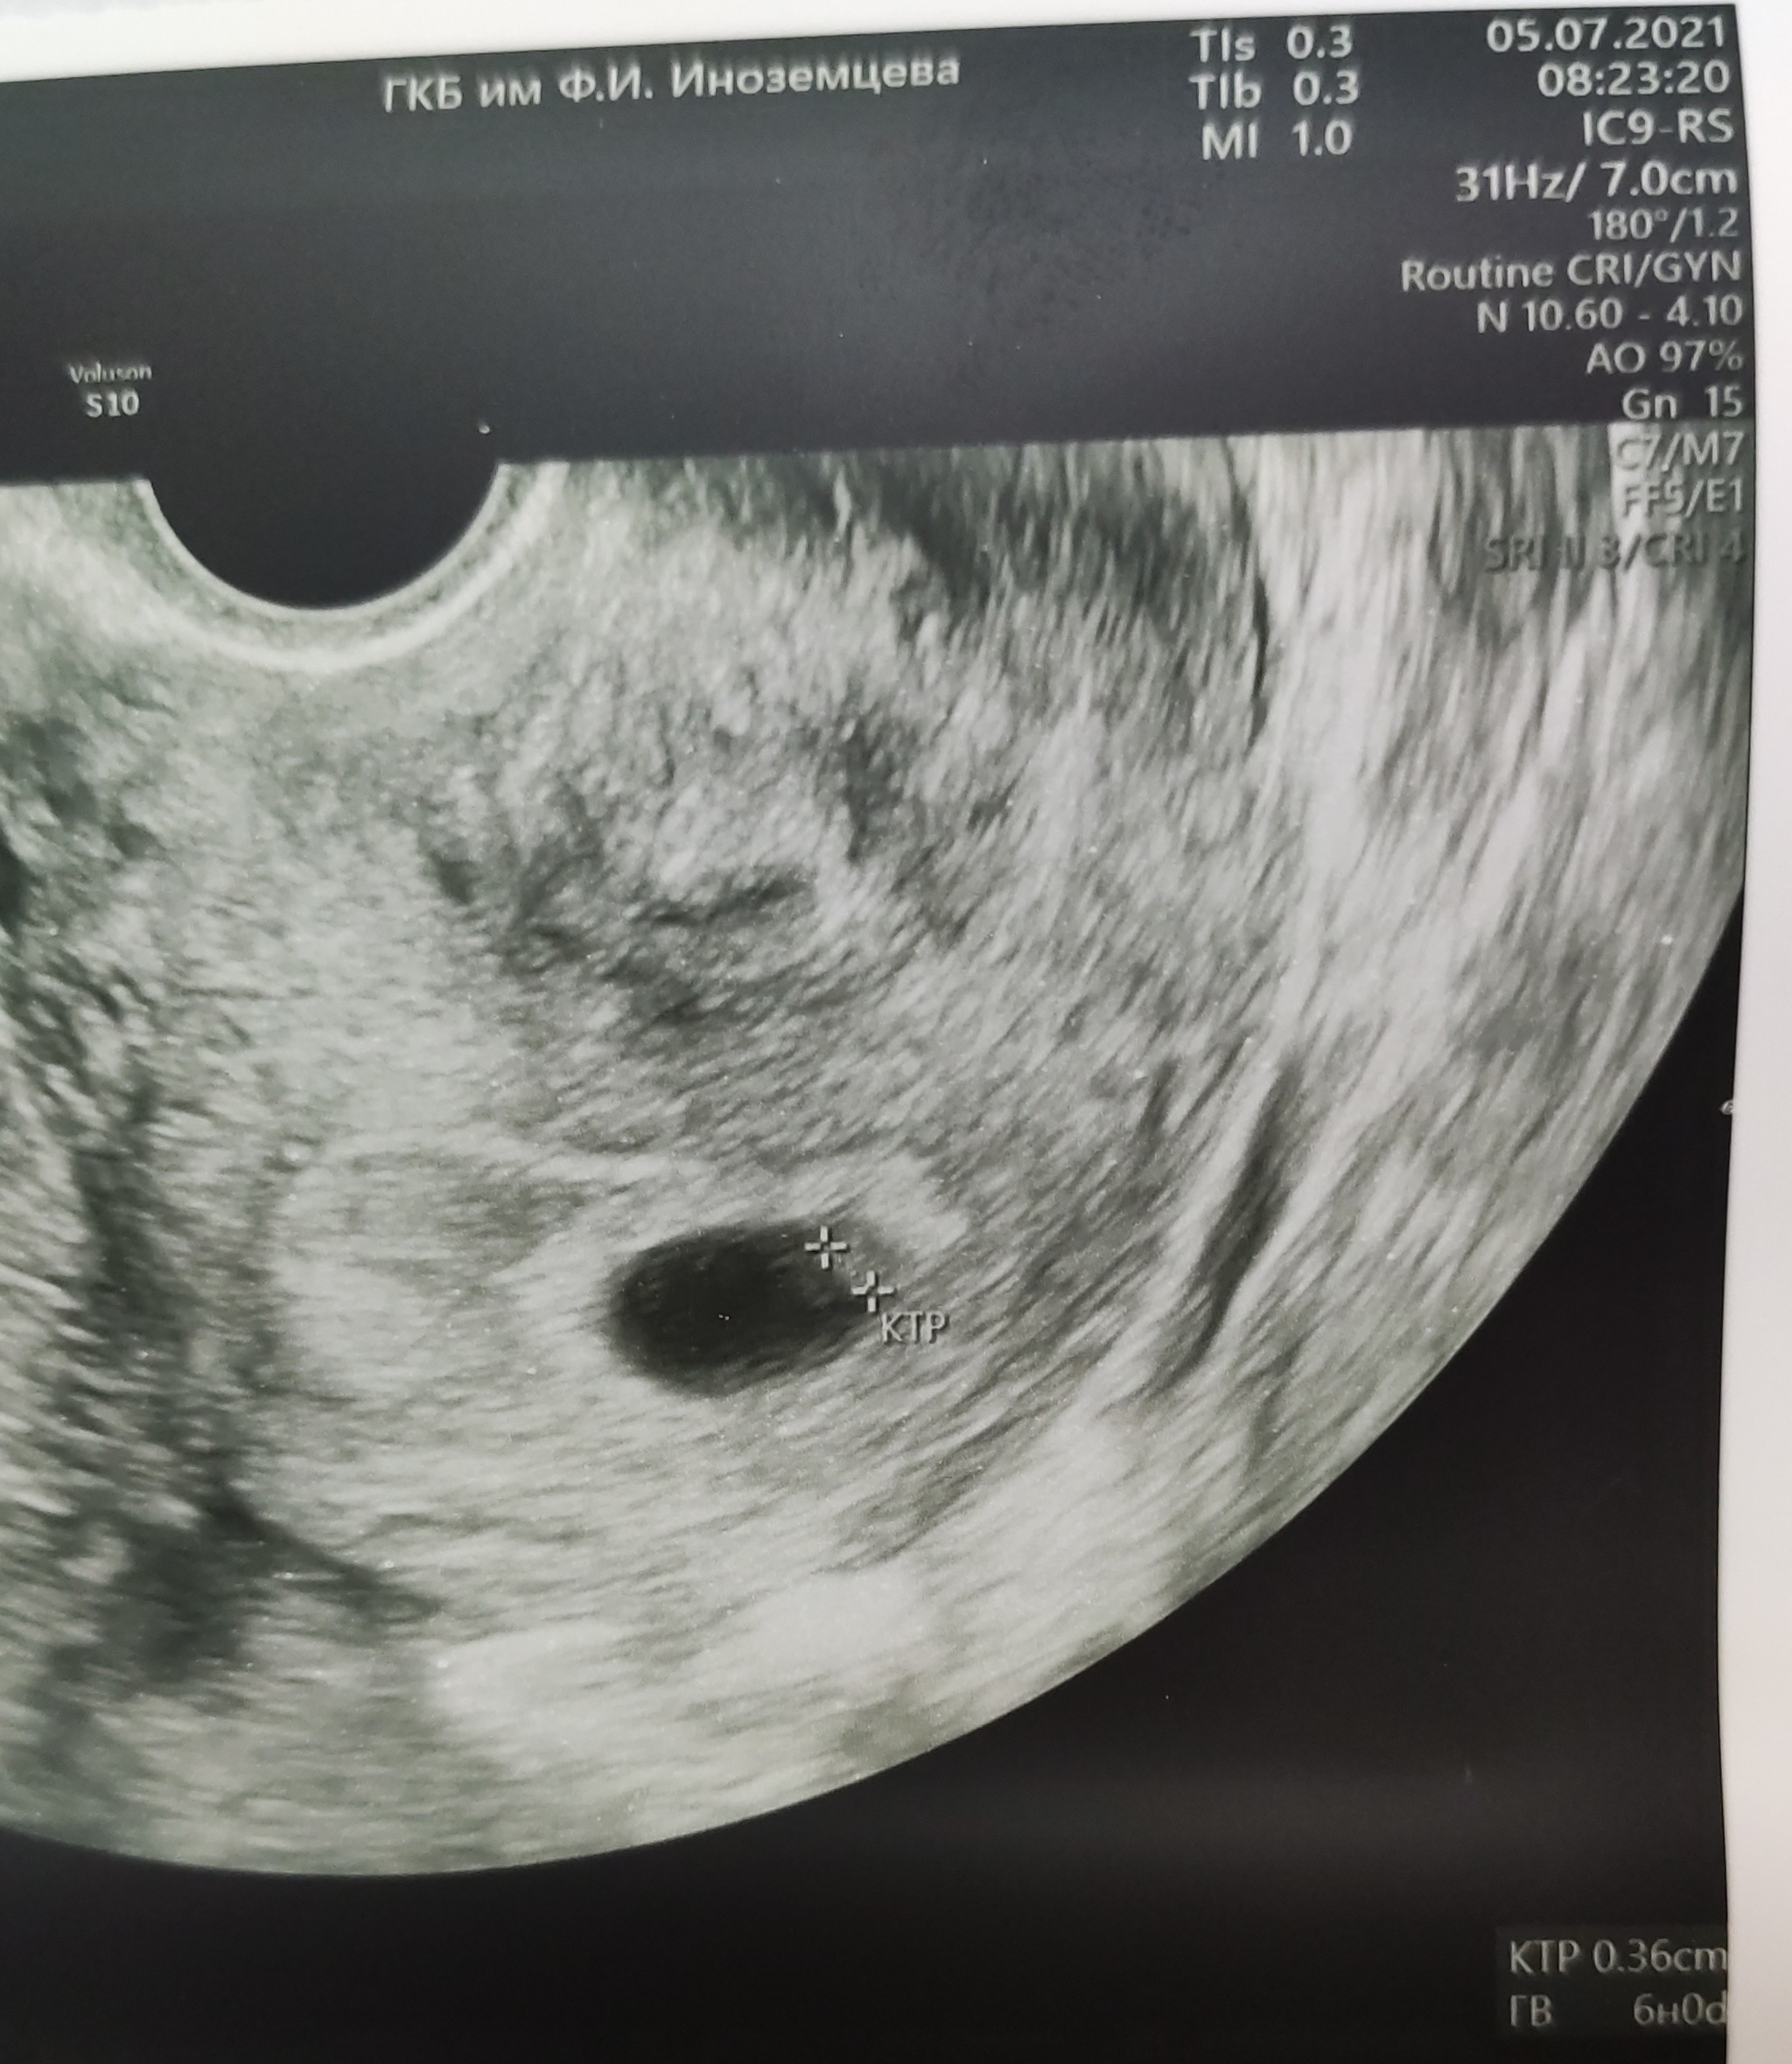

Вот так, с ооцита, окружённого питающими его клетками (кумулюс), и снующими рядом сперматозоидами начинается путь к новой жизни. Хотя в условиях ин витро возможны варианты с доставкой сперматозоида в ооцит, так сказать, бывает путь короче и легче)

При успешном оплодотворении на следующий день каждый из нас выглядел примерно вот так: